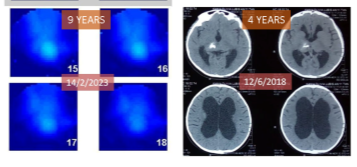

Recovering a Stolen Childhood: Defeating an Inoperable Brain Tumor

10 Years of Survival with Thalamic Cancer Without Surgery

In 2014, at just 8 years old, Kania was diagnosed with an inoperable low-grade glioma in the thalamus—the brain’s vital nerve center. The tumor caused severe hydrocephalus, seizures, and loss of motor function, but surgery was deemed impossible due to the high risk of damaging critical brain tissue. After rejecting invasive fluid drainage procedures, her family turned to ECCT in 2016. Despite the slow-growing nature of the tumor making it difficult to treat, the therapy successfully halted its progression and reduced the mass over time. Now 18 years old, Kania has defied her prognosis, returning to regular school and becoming a memorizer of the Qur’an, living proof that hope can be found even when medical options run out.